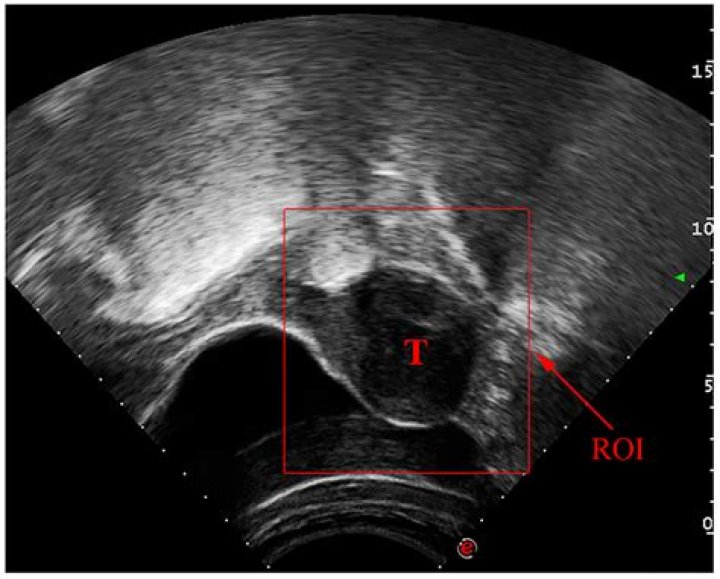

Read JournalLymph nodes in lymphomas may be indistinguishable from reactive lymph nodes in ultrasound, also with the application of color or power Doppler option (Fig...